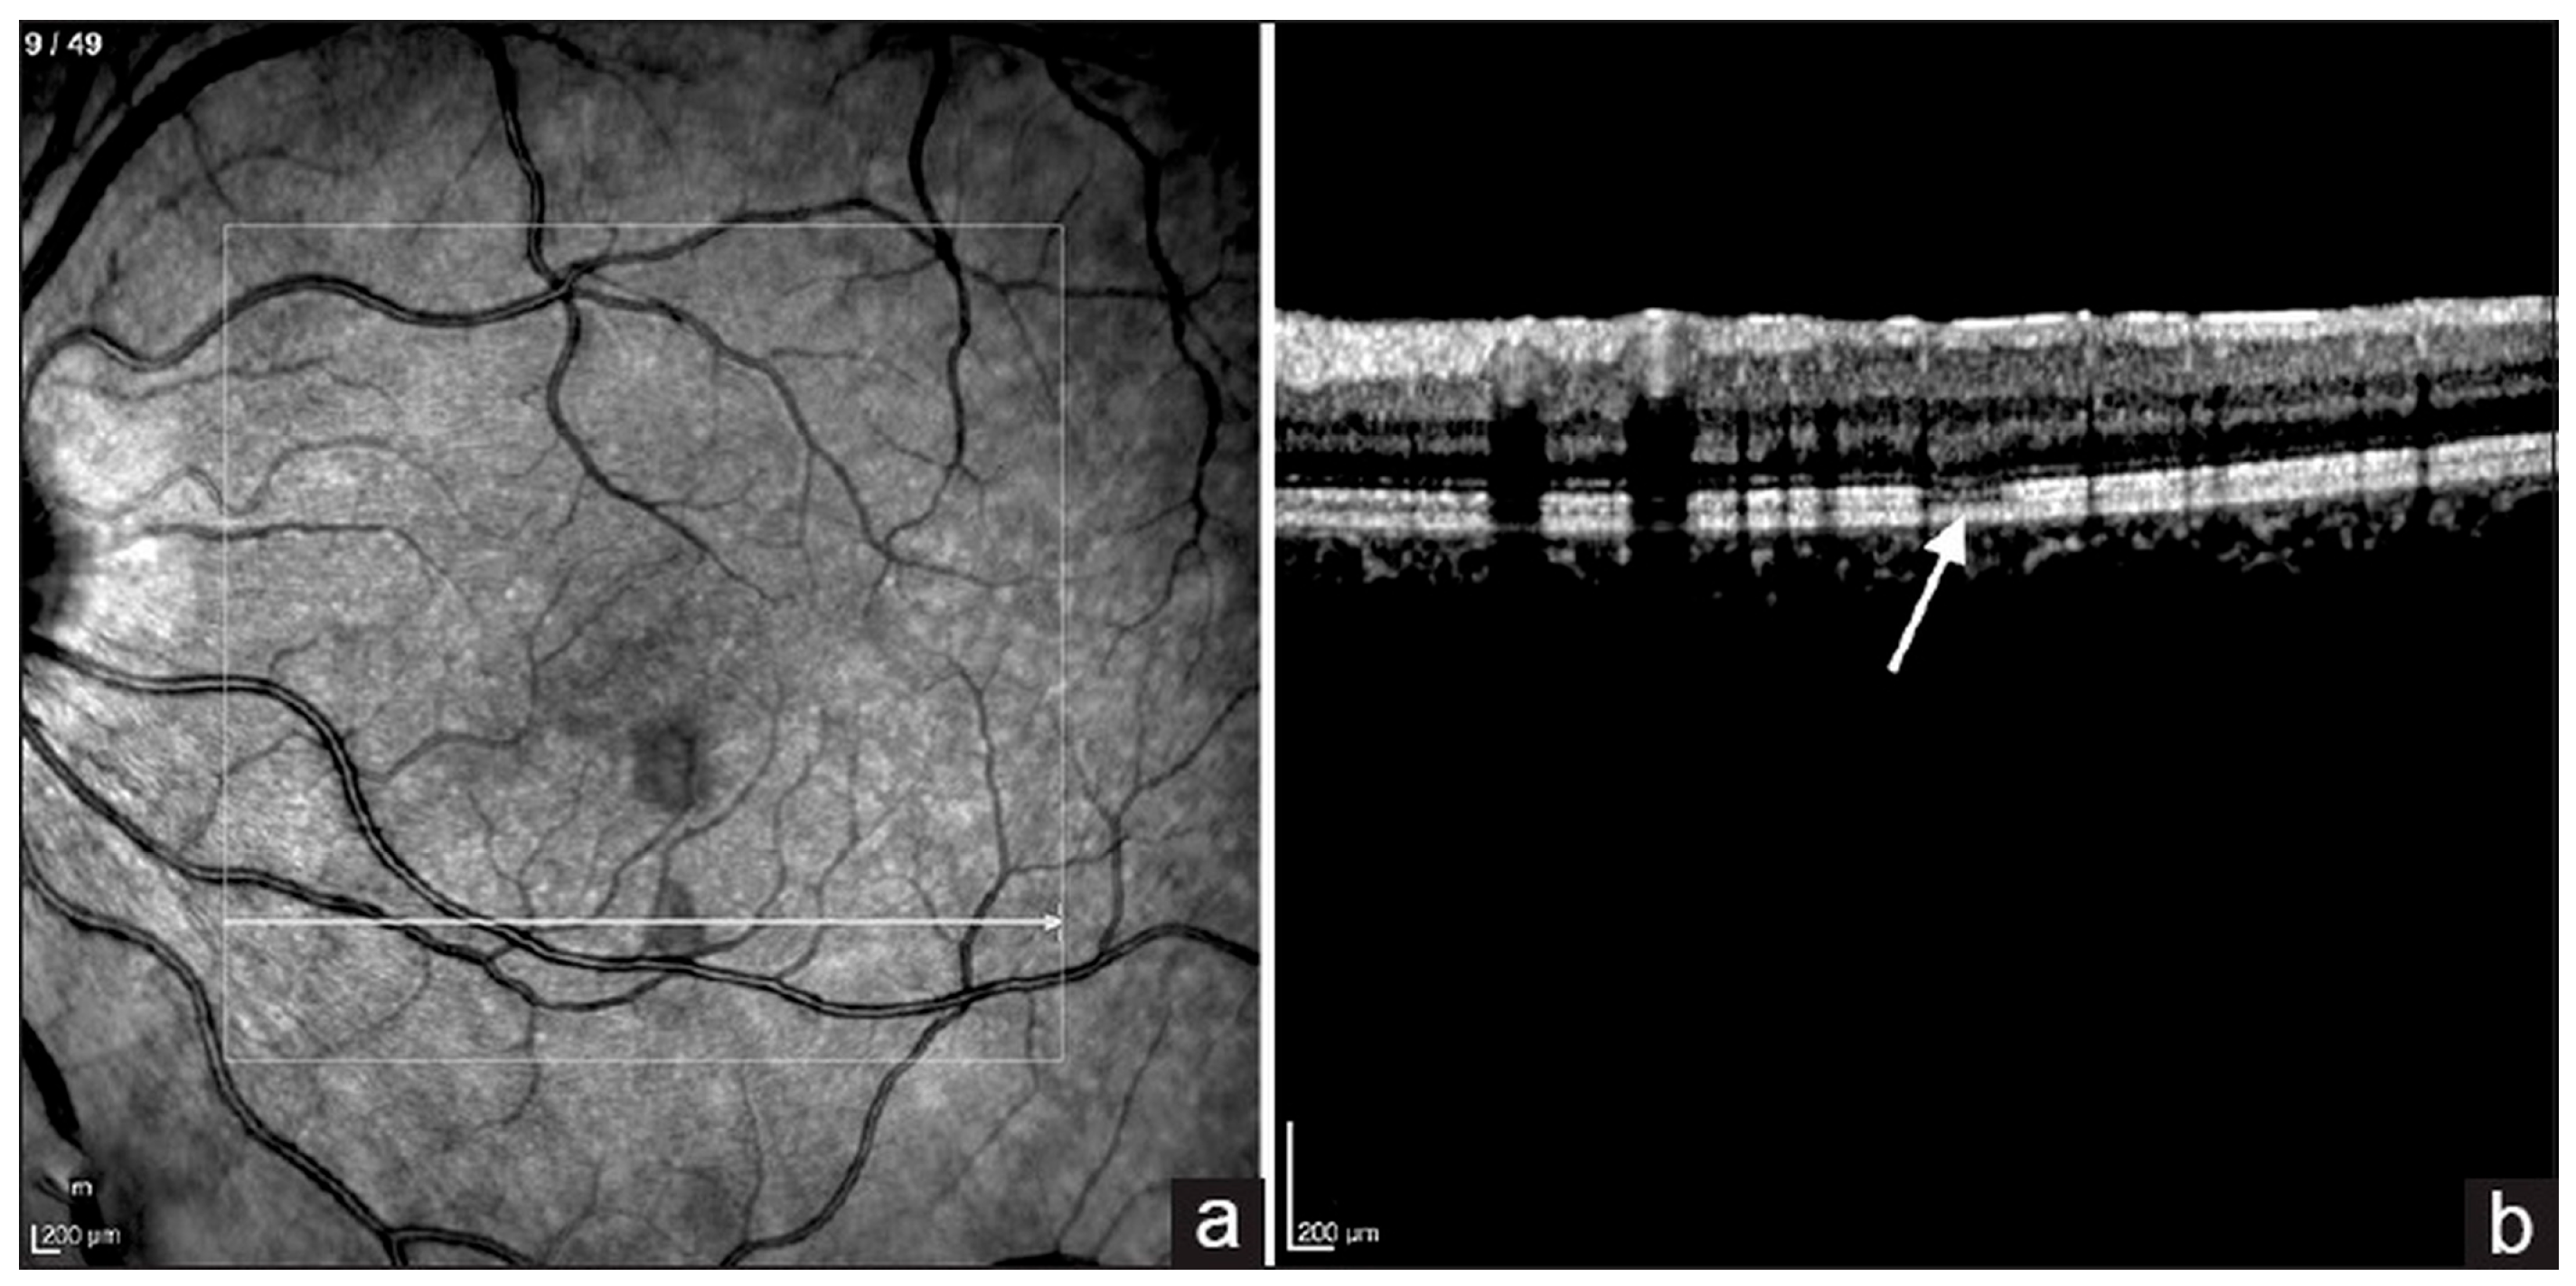

6.3. Optical Coherence Tomography (OCT)

6.6. Optical Coherence Tomography Angiography (OCTA)

- Mahendradas, P.; Acharya, I.; Rana, V.; Bansal, R.; Ben Amor, H.; Khairallah, M. Optical Coherence Tomography and Optical Coherence Tomography Angiography in Neglected Diseases. Ocul. Immunol. Inflamm. 2024, 32, 1427–1434. [Google Scholar] [CrossRef] [PubMed]